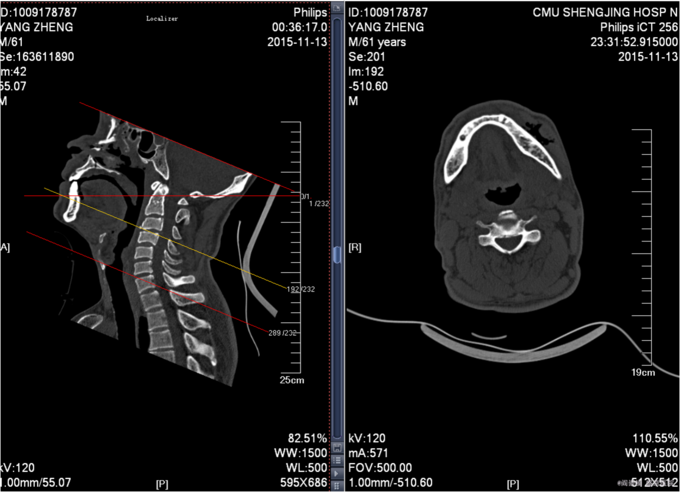

患者于2015年11月13日15:30左右因在工厂2米高管道上作业不慎坠落致颈部疼痛,四肢活动受限,受伤后被家人送入当地北台镇医院,输一袋葡萄糖液,转入本溪二院,行口腔科、眼科缝合行X线检查,头颅ct检查。患者及家属为求系统治疗,急来我院,急诊予以行辅助检查,提示:颈4-6棘突骨折,颅骨多发骨折;急诊以“颈椎外伤”为主诊断收入我科。病来患者一般状态无头晕及头痛,,无恶心及呕吐 ,留置导尿中。

前额部敷料包扎中,打开敷料见右眉处7cm大小创口已缝合,无渗出,前额处可见一5cm大小创口已缝合,颈领保护中,触痛。双手感觉减退。患者平乳头以下触觉存在,痛觉及运动消失。屈肘肌力(R4,L4),伸肘肌力(R0,L0),手掌掌屈肌力(R0,L0),手掌背伸肌力(R0,L0)。双手握力(R0,L0)。髂腰肌肌力(L0级,R0级),伸膝力(L0级,R0级),足背伸力(L0级,R0级),足跖屈肌力(L0级,R0级),神经反射:BCR:L(-)R(-),TCR:L(-)R(-),肱桡肌反射:(-)R(-),PSR: L(-)R(-),ASR: L(-)R(-),Hoffmann Sign:L(-)R(-), Babinski Sign L(-)R(-) 双侧桡动脉、足背动脉可扪及搏动,末梢血运良好。

患者入院后完善相关检查,明确诊断,手术指征明确,于2015-11-17日于全麻下行颈椎后路单开门椎板减压,侧块螺钉内固定术,术后经抗炎、止疼等对症治疗后,患者恢复顺利,切口愈合良好,今日可出院。